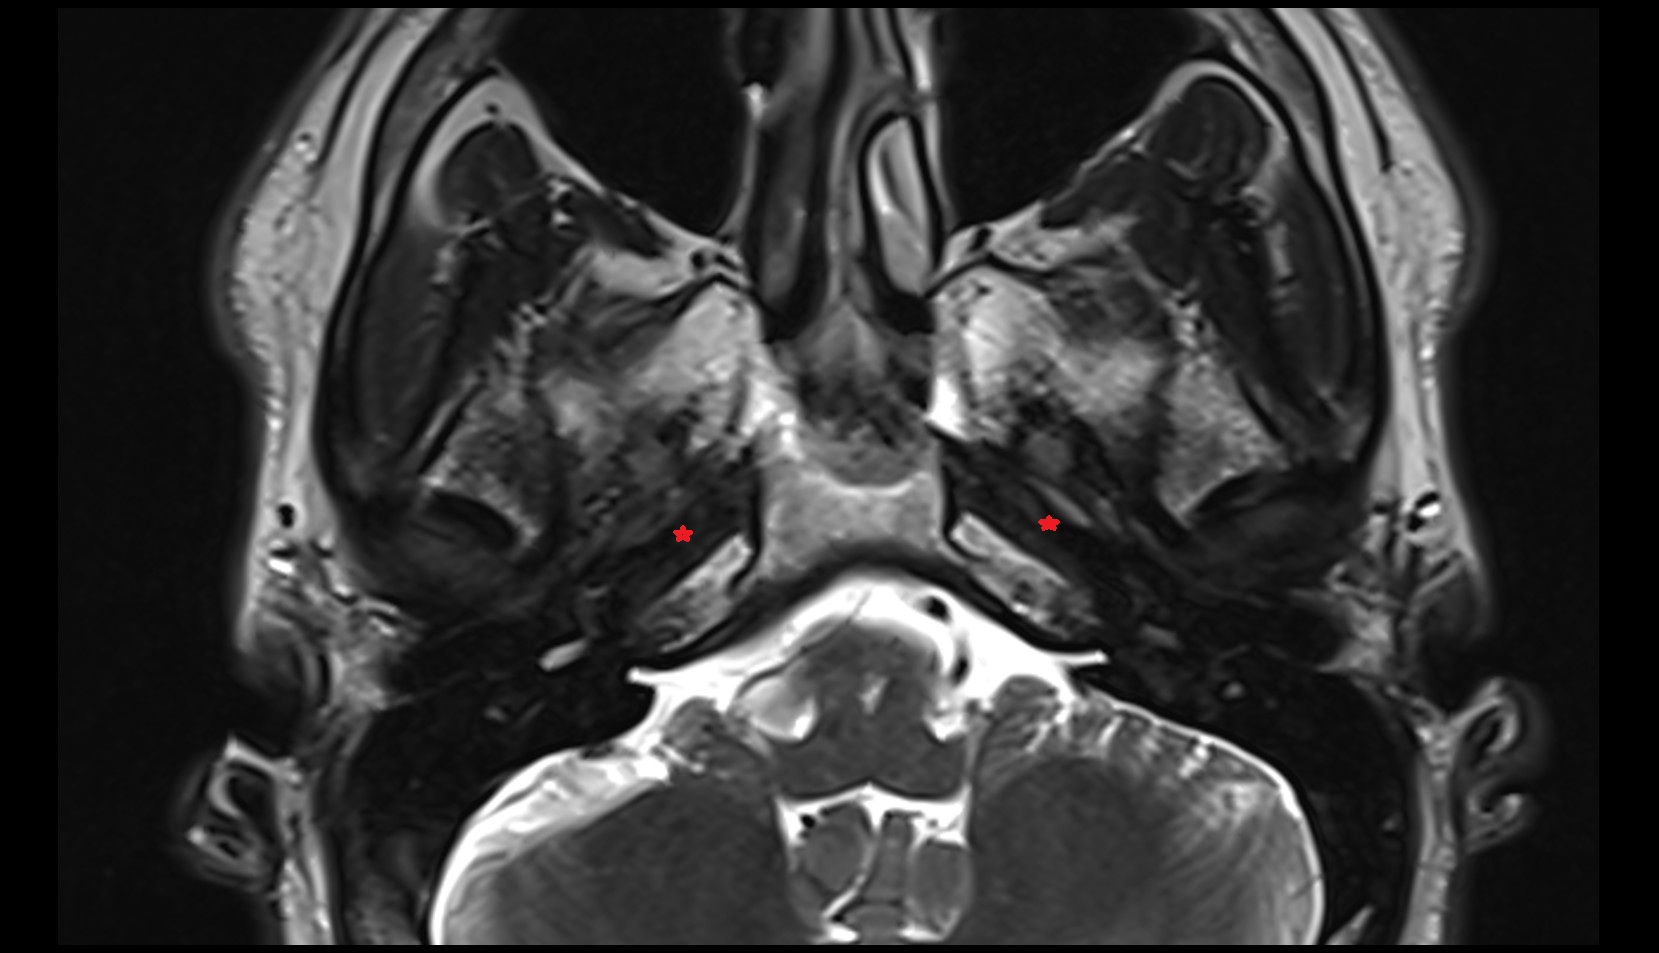

- Mandibular condyle

- Mandibular fossa

- Articular disc of temporomandibular joint

- Articular eminence